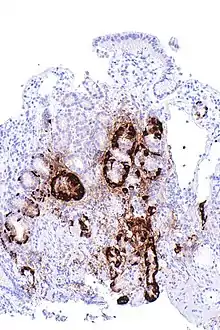

Micrograph showing nodular enterochromaffin-like cell hyperplasia, as demonstrated with chromogranin A immunostaining, in the body of the stomach. Parietal cells are not readily apparent. These changes are in keeping with autoimmune metaplastic atrophic gastritis, a histologic correlate of vitamin B12 deficiency anemia. | |

PA may be considered as an end stage of autoimmune atrophic gastritis, a disease characterised by stomach atrophy and the presence of antibodies to parietal cells and intrinsic factor.[36][37] Autoimmune atrophic gastritis, is localised to the body of the stomach, where parietal cells are located.[34] Antibodies to intrinsic factor and parietal cells cause the destruction of the oxyntic gastric mucosa, in which the parietal cells are located, leading to the subsequent loss of intrinsic factor synthesis. Without intrinsic factor, the ileum can no longer absorb the B12.[38] Atrophic gastritis is often a precursor to gastric cancer.[37]